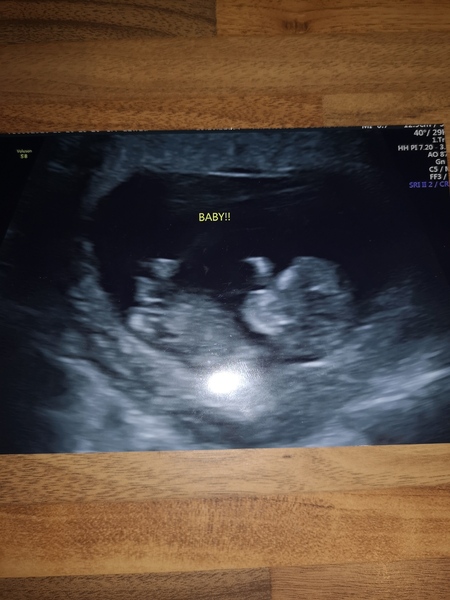

Had my second scan on Sunday! They bumped my dates up a bit so now 11+2. Got my booking in app on Monday and my 12 week scan next Monday so all go!

Hi ladies had my 12 wks scan & downs testing yesterday. All good & I'm measuring ahead so moved my due date to 30 April 2020 but please let me stay 😊.

@AmIseeingRight I just got moved forward 3 days too so we are now due date buddies! Congrats 💕 can you believe we’ve made it to 12 weeks?!

The nhs moved my due date to 2nd May which is very odd because baby was measuring 13 weeks on Tuesday and in the photo it even says 13 weeks, GA - 28/04/20! So I honestly don’t know when my due date is now - it doesn’t make sense!